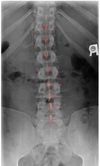

AP THORACIC LANDMARKS A-P thoracic

102

A-P thoracic

103

104

A-P thoracic view

105

106

LATERAL THORACIC LANDMARKS lateral thoracic view

108

Lateral thoracic view